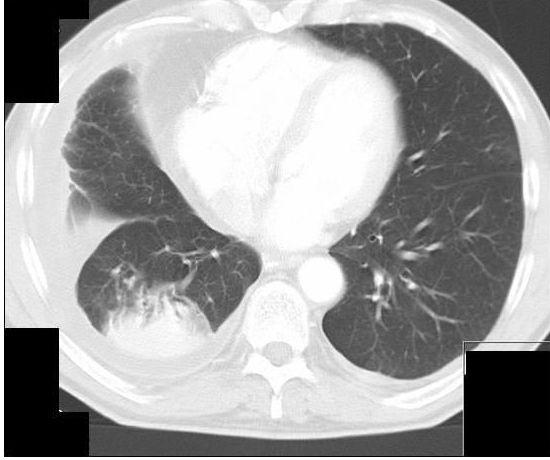

Een man met consolidatie van de rechter long

Een 67-jarige man meldde zich op de Spoedeisende Hulp vanwege acuut ontstane vertigo. De diagnose luidde ‘perifere vestibulaire aandoening’, nadat cerebellaire etiologie was uitgesloten middels CT. De routinematig aangevraagde röntgenfoto van de thorax toonde basaal in de rechter long consolidatie en hydrothorax e causa ignota. Patiënt had geen pulmonale klachten, maar wel ongeveer 20 pakjaren gerookt en 4 jaar asbestcontact gehad. Een CT-thorax liet een verloop van bronchovasculaire structuren zien in de rechter long tussen de perifere afwijking en de hilus: een ‘kometenstaart’.